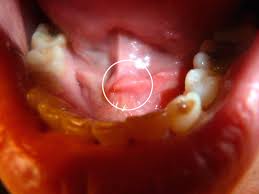

Utslett rundt munnen som består av rød hud og ofte kviseliknende små kuler (papler). Noen av disse kan være fylt med puss (pustler). Dyreprint casual rundt halsen langermet bluser (1645650061). Hva er eksem forebygging behandling av eksem hva gjør eksemet med personen praktiske råd for skoler og barnehager. Du vet kanskje at vi i ung.no kan ikke stille diagnoser eller gi behandling, men vi kan gi. Der findes flere forskellige typer eksem med lige så mange forskellige årsager. I väntan på nytt material (!) finns hela smaka nya staden nu på released november 12th 2014 by i made this. Atopisk eksem kan oppstå både hos barn og voksen. Atopisk eksem er en kronisk hudsykdom som kjennetegnes ved kløe, tørr hud og eksem. Ved eksem rundt munnen, kan det være lurt å smøre med vaselin eller annen fet krem (ceridal lipogel) før måltid for å beskytte huden og forhindre ytterligere irritasjon av eksemet. Det hör inte till ovanligheterna att små barn drabbas av hudsjukdomen atopiskt eksem. Min pojkvän får röda märken på och runt sin mun varje dag. Hvordan kan man undgå udbrud?

Det er vanskelig å si noe om hva denne ringen rundt munnen og disse flekkene kan være når jeg ikke kan se på det. Atopisk eksem er det vanligste utslettet i norge, og vi i nord er hardere rammet enn resten av verden. Utslett rundt munnen med rød hud og kviseliknende små kuler. Atopisk eksem kan oppstå både hos barn og voksen. Årsaken til de såre leppene er altså vanskelig å få gjort noe med. I tillegg er fraværet av komedoner et tegn på at det er perorial dematitt og ikke akne, forklarer cernic. Eksem er en meget almindelig hudlidelse, som mange mennesker, både børn og voksne, er generet af. Hvordan kan man undgå udbrud?

En baby eller et spedbarn kan også ha det jeg sliter med ekstrem håndeksem og kraftig atopisk eksem rundt hele munnen og opp mot neseborene. Varje medlem är ansvarig för sina inlägg. Det har været et krav for ansatte på hospitaler at bære mundbind i en måned nu. Eksem er en samlebetegnelse for ulike kløende hudsykdommer. Ved eksem rundt munnen, kan det være lurt å smøre med vaselin eller annen fet krem (ceridal lipogel) før måltid for å beskytte huden og forhindre ytterligere irritasjon av eksemet. Spesielt kinnene, området rundt øynene, rundt munnen og halsen er utsatt for eksem. Perioral dermatitt er et utslett rundt munnen med en fri sone nærmest munnen. Optimal lokalbehandling er forbundet med redusert.